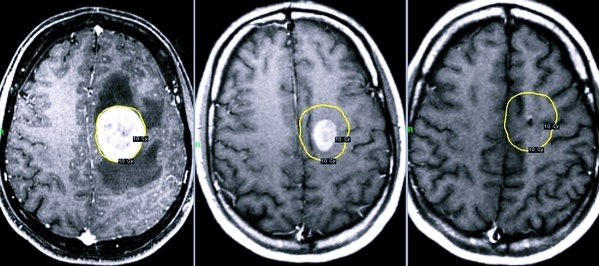

Для диагностики заболевания используются различные современные методы: МРТ, КТ, УЗИ и многие другие. Если форма патологии не молниеносная, то заподозрить наличие заболевания может невролог, который отметит прогресс ухудшения состояния больного, наращивание процессов нарушения сознания вместе с симптоматикой менингита.

Чтобы подтвердить диагноз, используются методы магнитно-резонансной и компьютерной томографии.

При отеке мозга крайне важно быстро установить причину развития патологии, а также начать лечение сопутствующей симптоматики. Поэтому после поступления в реанимацию врачи отслеживают у пациента работу сердца, симптомы интоксикации, температуру тела, проводят лечение антибиотиками, выводят токсины из организма, удаляют опухолевые новообразования.

Также медики часто делают операции по дренированию ликвора (для этого формируются обходные пути для течения спинномозговой жидкости). С точки зрения хирургии, эта процедура позволяет уменьшить внутричерепное давление, снизить отечность, частично обеспечить удаление отека. В послеоперационный период показана длительная реабилитация. При наличии онкологии (если это стало причиной появления отека) обязательно проводится лучевая терапия.